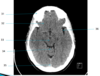

Head Flashcards

6

L occipital bone

7

L zygomatic arch

8

L lateral pterygoid plate

11

L Cerebellar tonsil

9

L lateral pterygoid muscle

1

R maxillary sinus

2

vomer

5

medulla oblongata

10

L mastoid air cells

14

R temporal lobe

3

nasopharynx

35

Superior sagittal sinus

4

R vertebral artery

12

lens of R eye

13

ethmoid air cells R

32

R frontal lobe

21

R zygomatic bone

37

Frontal horn of R lateral ventricle

17

internal occipital protuberance

19

basilar artery

22

R temporal bone

29

Pre pontine cistern

28

L anterior clinoid process

38

Septum pellucidum

33

Mid brain

15

pons

20

L occipital lobe

26

L optic nerve

18

R medial rectus muscle

44

Rt frontal lobe

41

Head of Lt caudate nucleus

16

4th ventricle

45

Falx cerebri

24

pons

40

Superior sagittal sinus

27

Sphenoid sinuses

36

Frontal bone, attachment of superior sagittal sinus

30

4th ventricle

43

Posterior horn Lt lateral ventricle

31

R frontal bone

23

pituitary fossa

42

Lt lentiform nucleus

46

Lt parietal lobe

25

R occipital bone

39

R thalamus

34

Cerebellar vermis